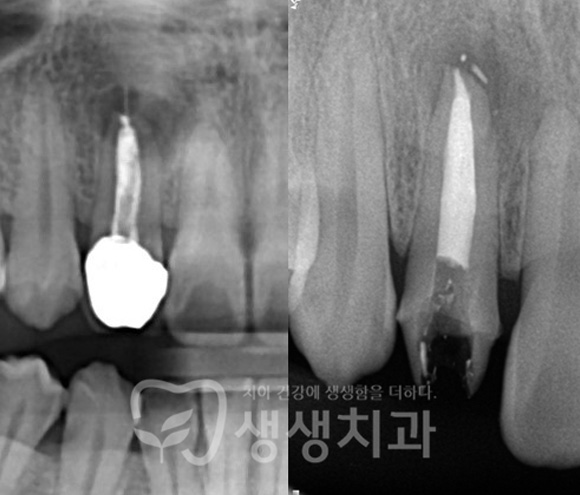

신경치료

재근관치료

만곡근관치료